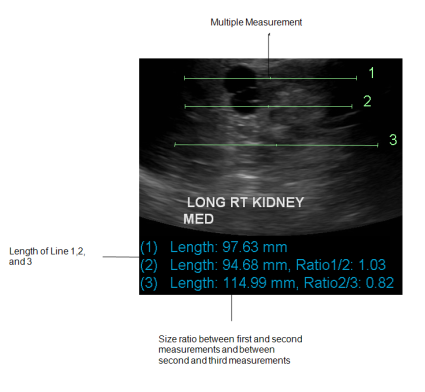

Linear measurement